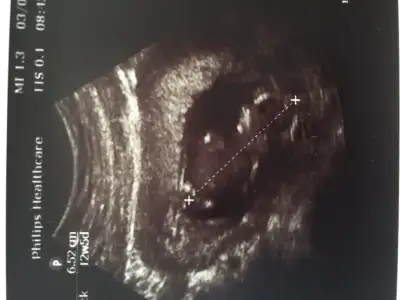

Kesin bişey demek istemedi doktorda,bacağını yukarı çekmişti hep net göremedim dedi sadece. Yakında öğreniriz bakalım :)) sağlıklı olsun kız erkek farketmez.. Teşekkür ederimm :)Çıkıntı yok zaten canım ama kimi doktor çıkıntı olmayinca da kız diyor erkek bariz belli oluyor.hayırlısı olsun inşallah

Baska resim var mı canım sırtı dönük tam çıkıntıya işaret koymuş

Kız sen nerden anlıyon sırtı dönük. Ben hiçbişi görmüyomBaska resim var mı canım sırtı dönük tam çıkıntıya işaret koymuş

Hatta burda kesenin Altın'da kanama var dediBaska resim var mı canım sırtı dönük tam çıkıntıya işaret koymuş